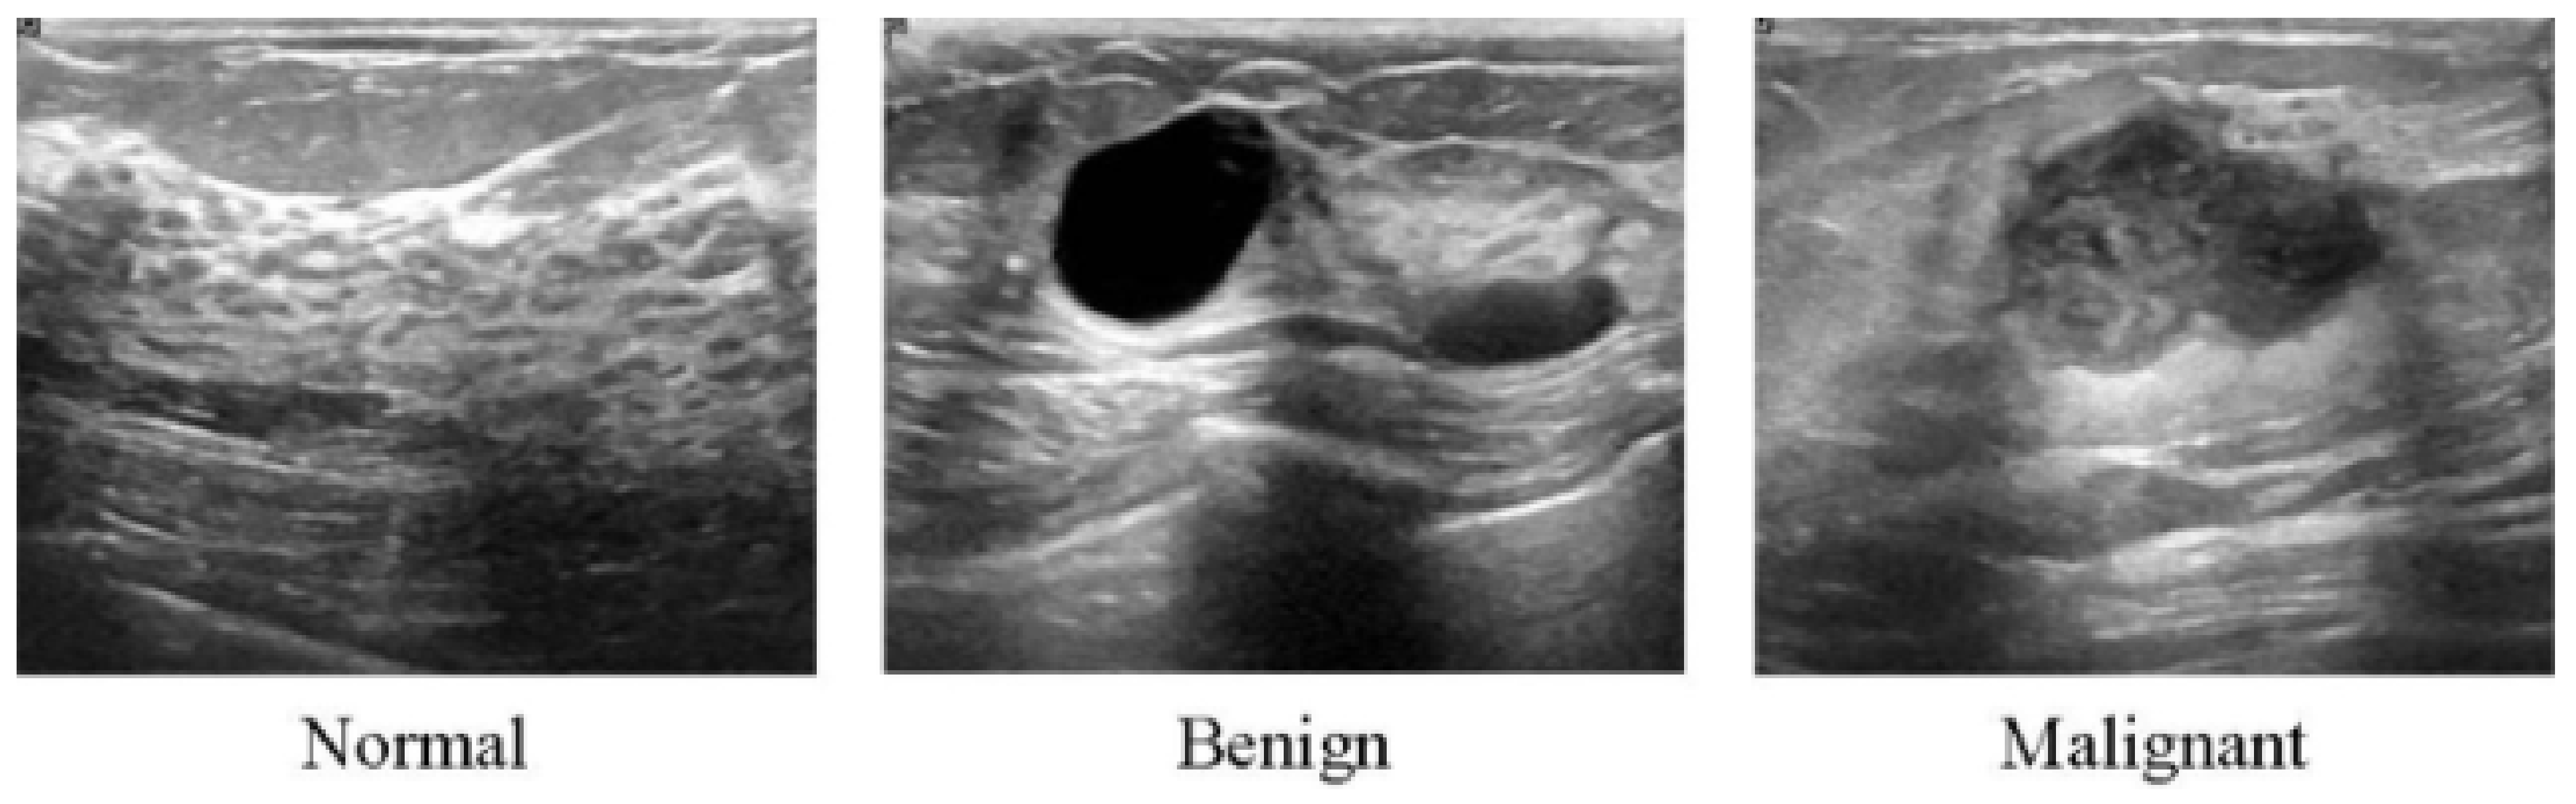

All of the aforementioned modalities can endanger patients and radiologists because of possible overdosage of ionizing radiation, making these approaches slightly risky and unhealthy for certain sensitive patients [62]. Additionally, these methods show low specificity, meaning the low ability to correctly determine a tissue without disease as a negative case. Therefore, although the aforementioned imaging modalities are highly used for early breast cancer detection, the US as a safe imaging modality has been used [62,63,64,65,66,67] (Figure 3). Compared to MMs, the US is a more convenient method for women with dense breasts. It is also useful to characterize abnormal regions and negative tumors detected by MMs [68]. Some studies showed the high accuracy of the US in detecting and discriminating benign and malignant masses [69]. US images are used in three broad combinations, i.e., (i) simple two-dimensional grayscale US images, (ii) color US images with shear wave elastography (SWE) added features, and (iii) Nakagami colored US images without any need for ionizing radiation [70,71]. It is worth noting that Nakagami-colored US images are responsible for the region of interest extraction by better detection of irregular masses in the breast. Moreover, US can be used as a complement to MMs owing to its availability, inexpensiveness compared to other modalities, and it being well tolerated by patients [70,72,73]. In a recent retrospective study, US breast imaging has shown high predictive value when combined with MMs images [74]. US images, along with MMs, improved the overall detection by about 20% and decreased unnecessary biopsy tasks by 40% in total [67]. Moreover, US is a reliable and valuable tool for metastatic lymph node screening in breast cancer patients. It is a cheap, noninvasive, easy-to-handle and cost-effective diagnostic method [75]. However, the US represents some limitations. For instance, the interpretation of US images is highly difficult and needs an expert radiologist to comprehensively understand these images. This is because of the complex nature of US images and the presence of speckle noise [76,77]. To deal with this issue, new technologies have been introduced in breast US imaging, such as automated breast ultrasound (ABUS). ABUS produces 3D images using wider probes. Shin et al. [78] improved how ABUS allows more appropriate image evaluation for large breast masses compared to conventional breast US. On the other hand, ABUS showed the lowest reliability in the prediction of residual tumor size and pCR (pathological complete response) [79]. Table 1 highlights more details about the weaknesses and strengths of the US imaging modality.

3.2.2. Ultrasound (US)

As has been explained in Section 2, ultrasound performs much better in detecting cancers and reduces unnecessary biopsy operations [183]. Therefore, it is not surprising to see that the researchers use this type of image in their DL models for cancer detection [184,185,186]. For instance, a GoogleNet [187]-based CNN has been trained on the suspicious ROIs of US images in [184]. The proposed method in [184] achieved an AUC of 96%, which is 6% higher than the CAD-based method with hand-crafted features. The authors in [188,189,190] trained CNN models directly with whole US images without extracting the ROIs. For example, the authors in [190] combined VGG19 and ResNet152 and trained the ensemble network on US images. Their proposed method achieved an AUC of 95% on a balanced, independent test dataset. Figure 8 represents an example of CNN models for breast cancer subtype classification.

In comparison with datasets for mammography images, there are fewer datasets for US images, and they usually contain much fewer images. Therefore, most of the proposed DL models use some kind of data augmentation method, such as rotation, to increase the size of training data and improve the model performance. However, one should be careful about how to augment US images since some augmentation may decrease the model performance. For example, it has been shown in [186] that performing the image rotation or shift in the longitudinal direction can affect the model performance negatively. The generative adversarial networks (GANs) can also be used to generate synthetic US images with or without tumors [191]. These images can be added to the original training images to improve the model’s accuracy.

The US images have also been used in lesion detection in which, when given an image, the CAD system decides whether the lesion is present. One of the challenges that the researcher faces in this type of problem with normal US images is that there is a need for a US doctor to manually select the images that have lesions for the models. This depends on the doctors’ availability and is usually expensive and time-consuming. It also adds human errors to the system [192]. To solve this problem, a method has been developed in [193] to detect the lesions in real time during US scanning. Another type of US imaging is called the 3D automated breast US scan, which captures the entire breast [194,195]. The authors in [195] developed a CNN model based on VGGNet, ResNet [196], and DenseNet [197] networks. Their approach obtained an AUC of 97% on their private dataset and an AUC of 97.11% on the breast ultrasound image (BUSI) dataset [80].

Some methods combined the detection and classification of lesions in US images in one step [198]. An extensive study in [199] compares different DL architectures for US image detection and classification. Their results show that the DenseNet is a good candidate for classification analysis of US images, which provides accuracies of 85% and 87.5% for full image classification and pre-defined ROIs, respectively. The authors in [200] developed a weakly supervised DL algorithm based on VGG16, ResNet34, and GoogleNet trained using 1000 unannotated US images. They have reported an average AUC of 88%.

Some studies validate the performance of DL algorithms [201,202,203] using expert inference, showing that DL algorithms can greatly help radiologists. This is mostly in cases where the lesion was already detected by an expert, and the DL model is used to classify them. However, unlike the mammography studies, most of the studies are not validated by multiple physicians and do not show the generalizability of their method on multiple datasets which should be addressed in future validations. Table 4 shows the list of recent algorithms used for US images and their performances.